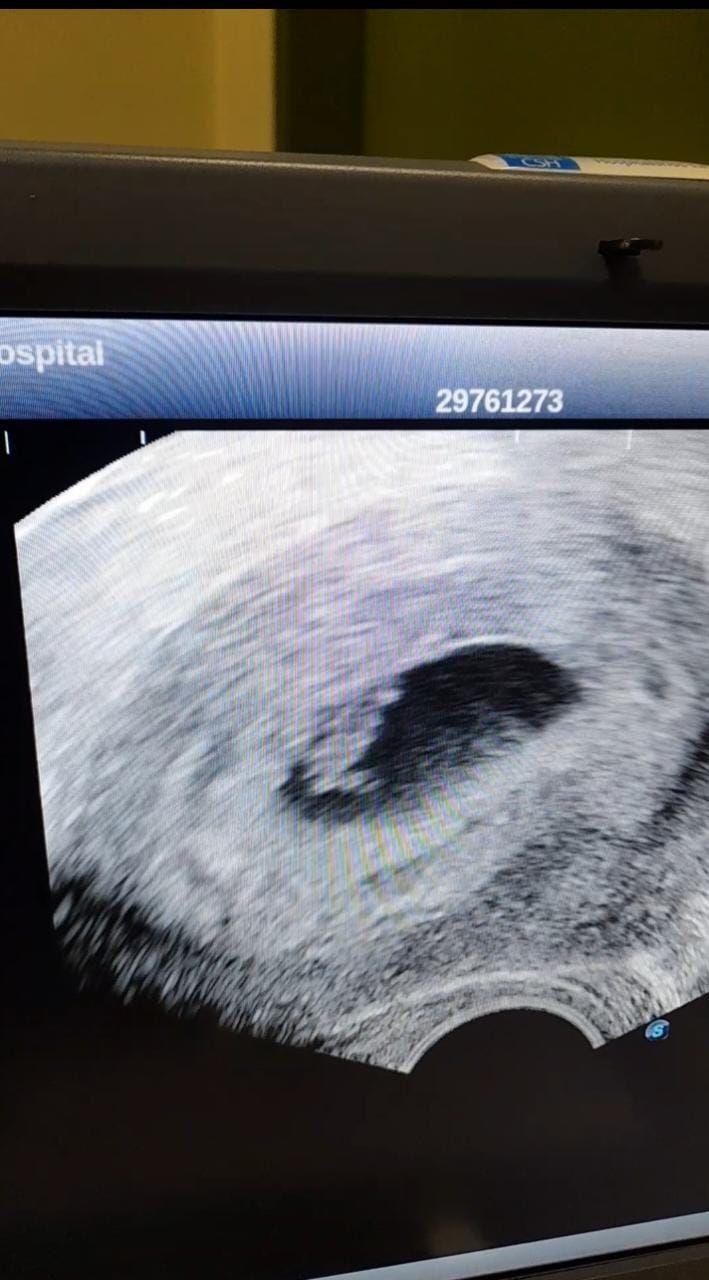

Ese día, muy temprano, se hizo el test y dio positivo. Empezó a gritar y Mauricio saltó de la cama. Seguía pensando que podía ser una ilusión. “Tengo tanta mala suerte , que por el COVID me dio cáncer”, dijo Sthefi, porque entre tanto que había estudiado sobre infertilidad, una vez leyó que un tipo de cáncer puede dar resultado positivo en el test. En la sección de Fertilidad le hicieron una ecografía. Allí confirmaron: embrión de 7 semanas y media bien implantado.